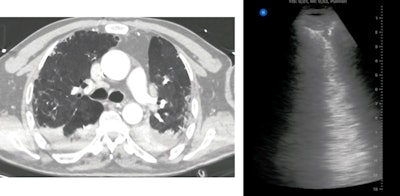

Ground glass on CT (left). Confluent B-lines on ultrasound (right). All images courtesy of Dr. Yale Tung Chen.

Ground glass on CT (left). Confluent B-lines on ultrasound (right). All images courtesy of Dr. Yale Tung Chen. Crazy paving, consolidation, and ground glass on CT (left). Irregular pleural line, subpleural consolidation, and confluent B-lines on ultrasound (right).

Crazy paving, consolidation, and ground glass on CT (left). Irregular pleural line, subpleural consolidation, and confluent B-lines on ultrasound (right).Chen conducted point-of-care ultrasound scans on all patients using a 12-zone protocol. Each zone was assigned a lung ultrasound score (LUS), with higher scores indicating more severe disease.